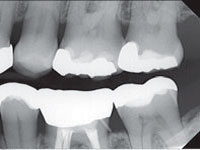

Цифровая  компьютерная   диагностика.

В нашей работе мы используем радиовизиограф HELIODENTPLUS – это интраоральная рентгенографическая система новейшего поколения немецкой фирмы «Sirona» дающая  высокое качество изображения при минимальной дозе облучения, что позволяет нам проконтролировать качество проведенного лечения.

Рентгеновские изображения, полученные на HELIODENT

PLUS, характеризуются высокой детализацией и контрастностью, что позволяет использовать их по широкому ряду показаний.